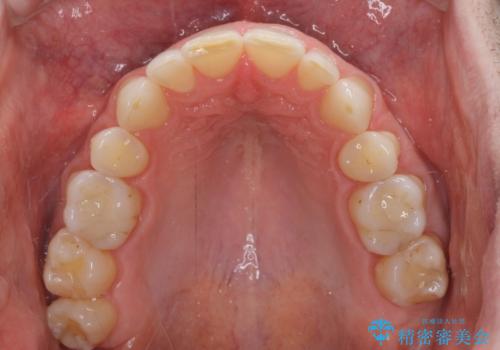

- 上下前歯の叢生を気にして来院された患者様です。

抜歯矯正をした後戻りということで、歯列不正はそれほど大きくなかったため、インビザライン・ライトを用いて矯正治療を行うこととしました。

前歯のデコボコが残っており、シミュレーション通りに動いていない部分がありましたが、再矯正であることやご本人の満足いくところまでデコボコが改善されたとのことで、治療を終了することとしました。